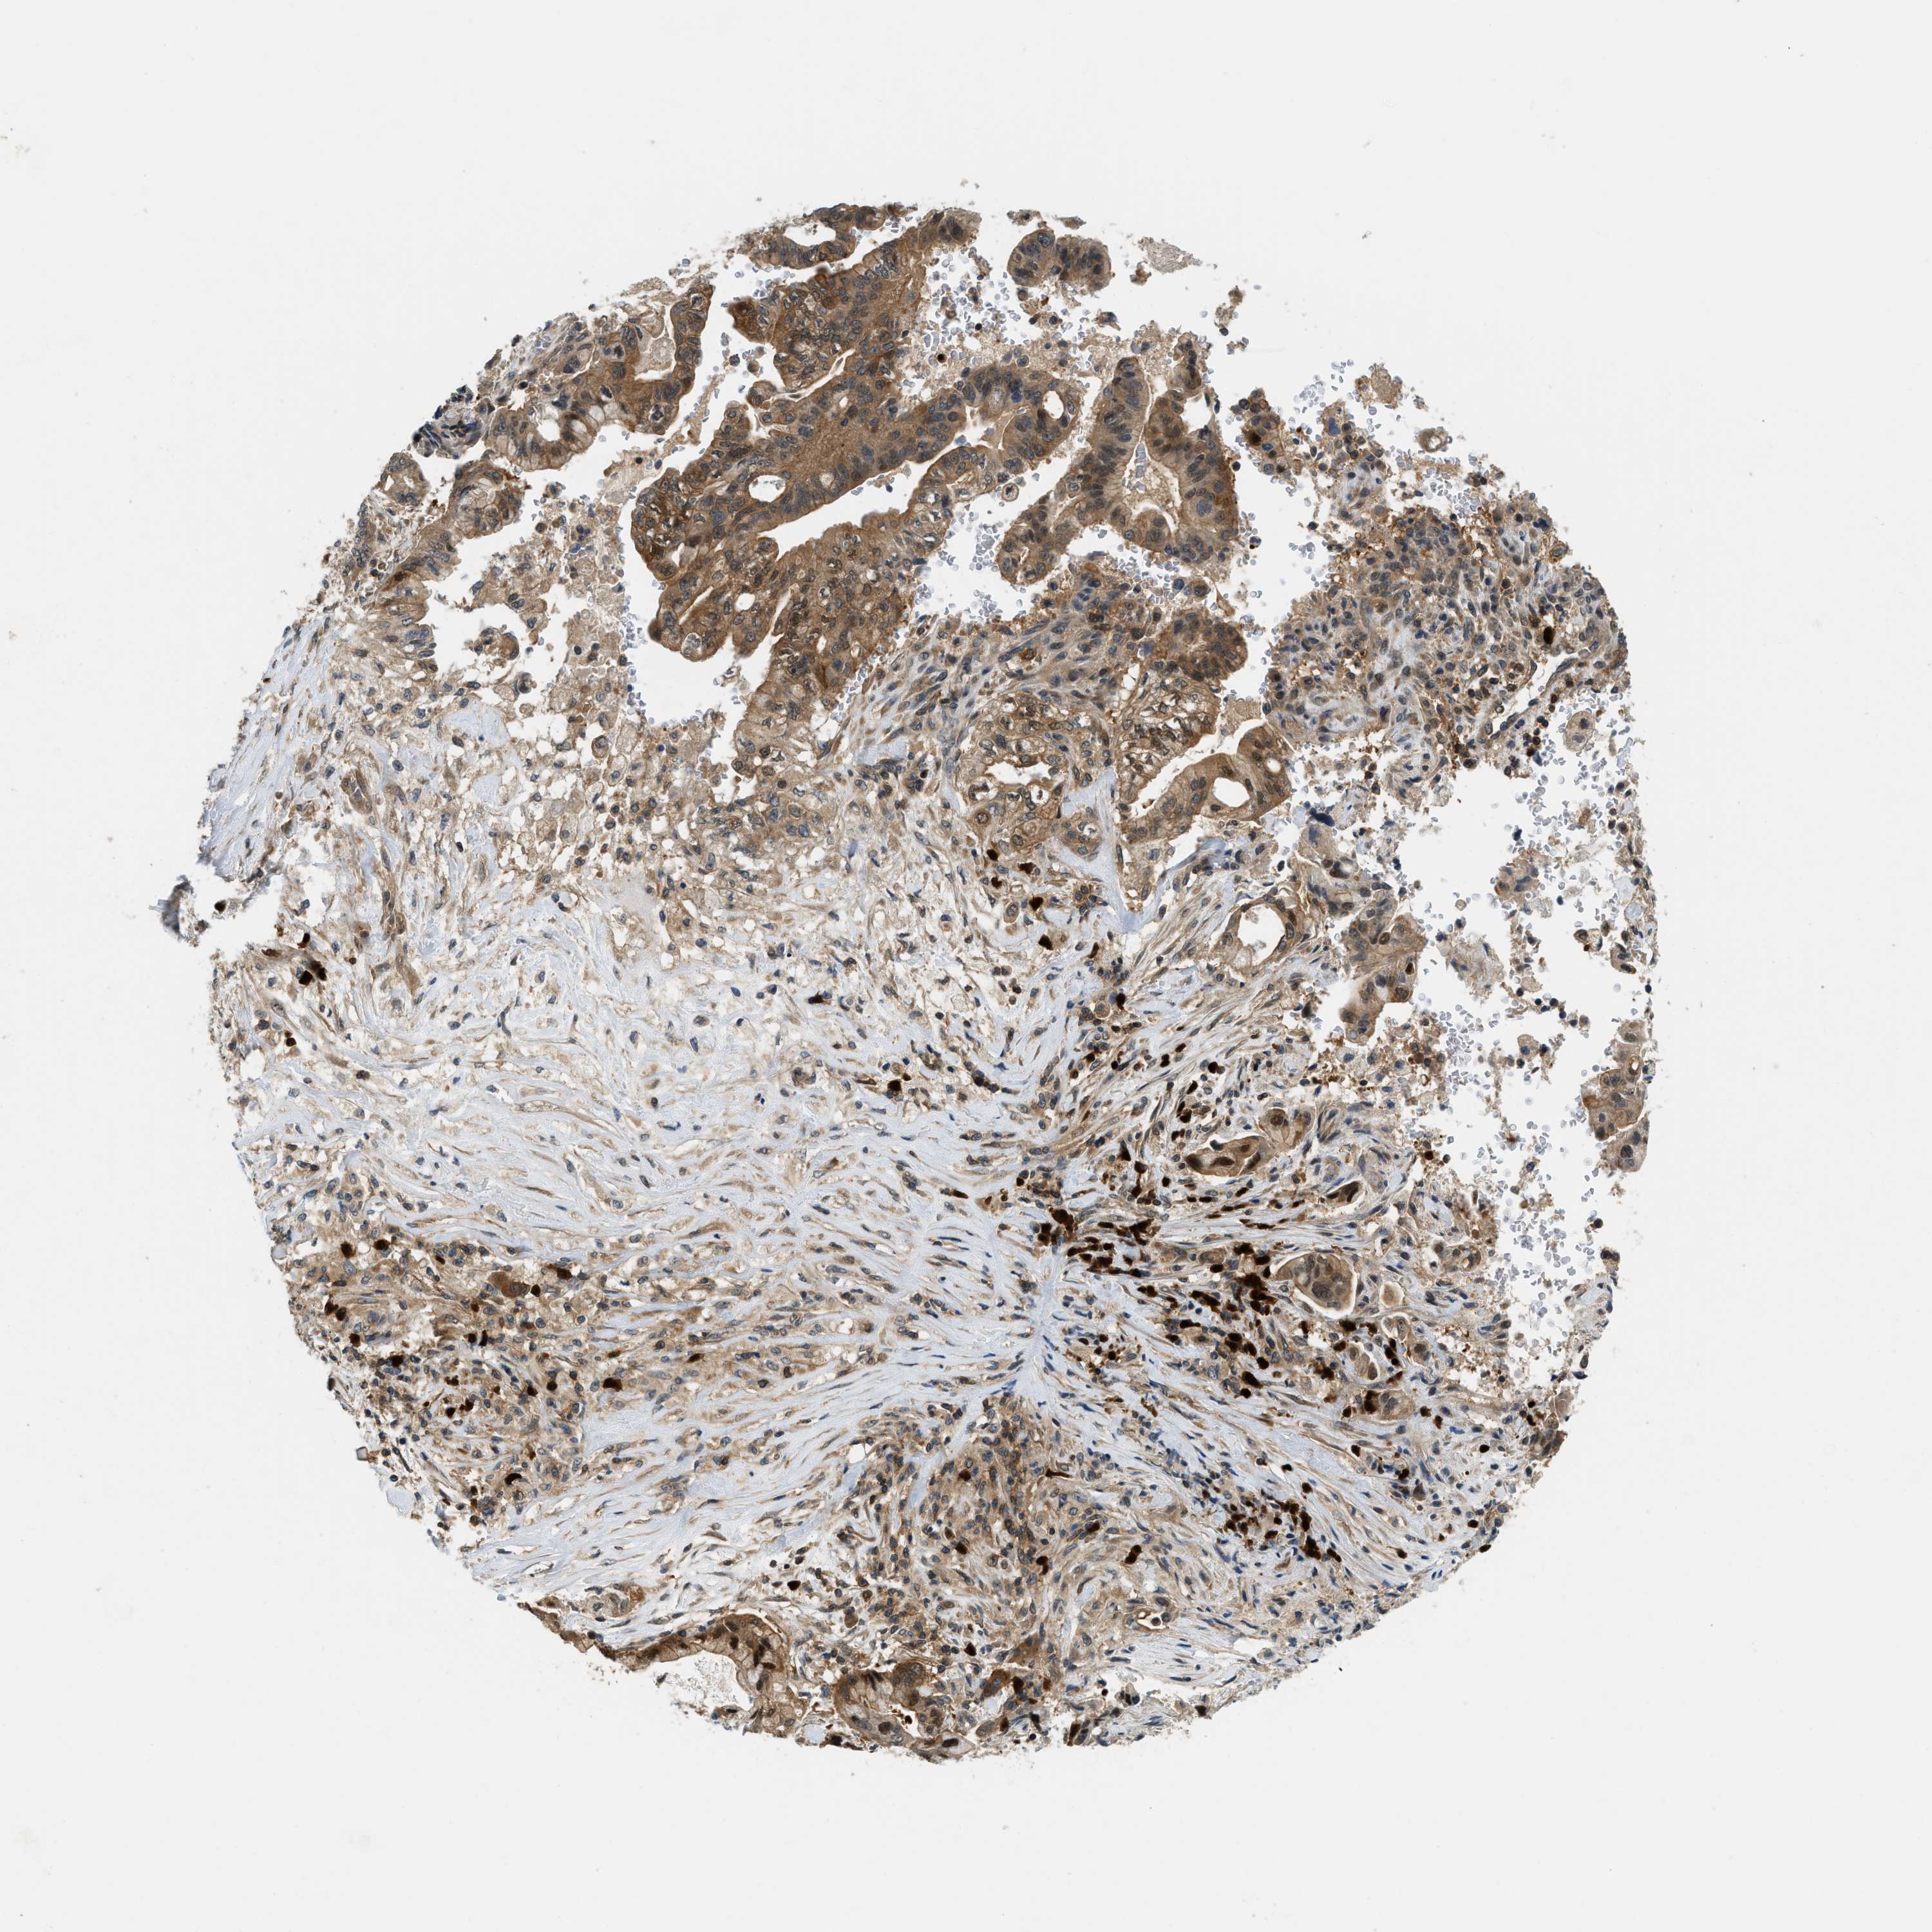

PANCREATIC CANCER - Protein expressioni

A mouse-over function shows sample information and annotation data. Click on an image to view it in a full screen mode. Samples can be filtered based on level of antibody staining by selecting one or several of the following categories: high, medium, low and not detected. The assay and annotation is described here.

Note that samples used for immunohistochemistry by the Human Protein Atlas do not correspond to samples in the TCGA dataset.

Antibody stainingi

Antibody staining in the annotated cell types in the current human tissue is reported as not detected, low, medium, or high, based on conventional immunohistochemistry profiling in selected tissues. This score is based on the combination of the staining intensity and fraction of stained cells.

Each image is clickable and will lead to virtual microscopy that enables deeper exploration of all samples and also displays staining intensity scores, fraction scores and subcellular localization as well as patient and tissue information for each sample.

Antibody HPA014657

Staining

High

Medium

Low

Not detected

Intensity

Strong

Moderate

Weak

Negative

Quantity

>75%

75%-25%

<25%

None

Location

Nuclear

Cytoplasmic/membranous

Cytoplasmic/membranous,nuclear

Adenocarcinoma, NOS